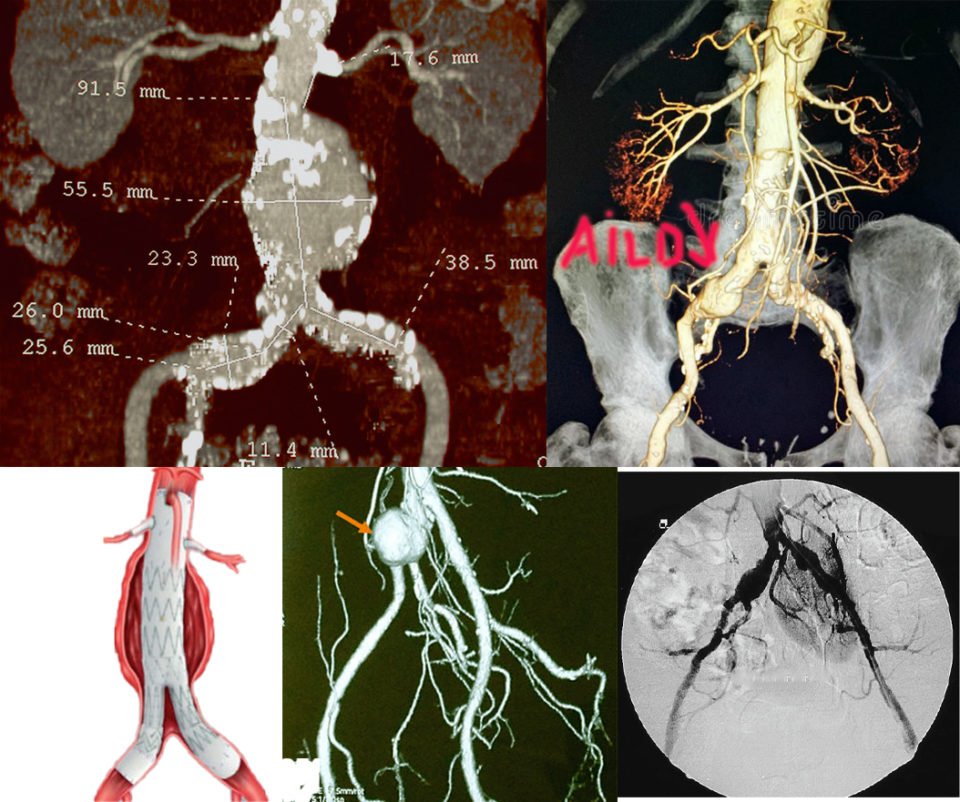

L’aorte est le plus gros vaisseau de l’organisme, sa partie située dans l’abdomen se divise en deux artères iliaques pour apporter le sang aux 2 membres inférieurs. L’anévrisme de l’aorte abdominale est une dilatation ou une augmentation de calibre de l’aorte abdominale. On parle d’anévrisme lorsque le diamètre de l’aorte mesure plus de 30 mm (3 cm) et d’anévrysme iliaque lorsque le diamètre de l’artère iliaque mesure plus de 20 mm (2 cm).

La grande majorité (85%) des anévrismes de l’aorte abdominale est située sous les artères rénales et les artères iliaques sont souvent aussi anévrismales. Si l’anévrisme englobe l’origine des artères rénales, on parle alors d’anévrisme pararénal.

L’angioscanner aorto-iliaque est plus invasif mais plus reproductible que l’échographie et moins opérateur dépendant. C’est l’examen de choix avant un traitement par endoprothèse ou par chirurgie classique. Il permet les mesures exactes (« sizing ») de l’anatomie de l’anévrysme, de l’aorte et des artères iliaques avant mise en place d’une endoprothèse. Il permet la recherche d’autres anévrysmes au niveau fémoro-poplités et d’étudier l’ensemble de l’aorte.

Il existe deux types de traitement qui sont détaillés sur ce site, le traitement chirurgical classique et le traitement mini-invasif par endoprothèse. Le traitement mini invasif par endoprothèse est de plus en plus utilisé, on estime qu’il est utilisé dans 70% à 80% des cas.